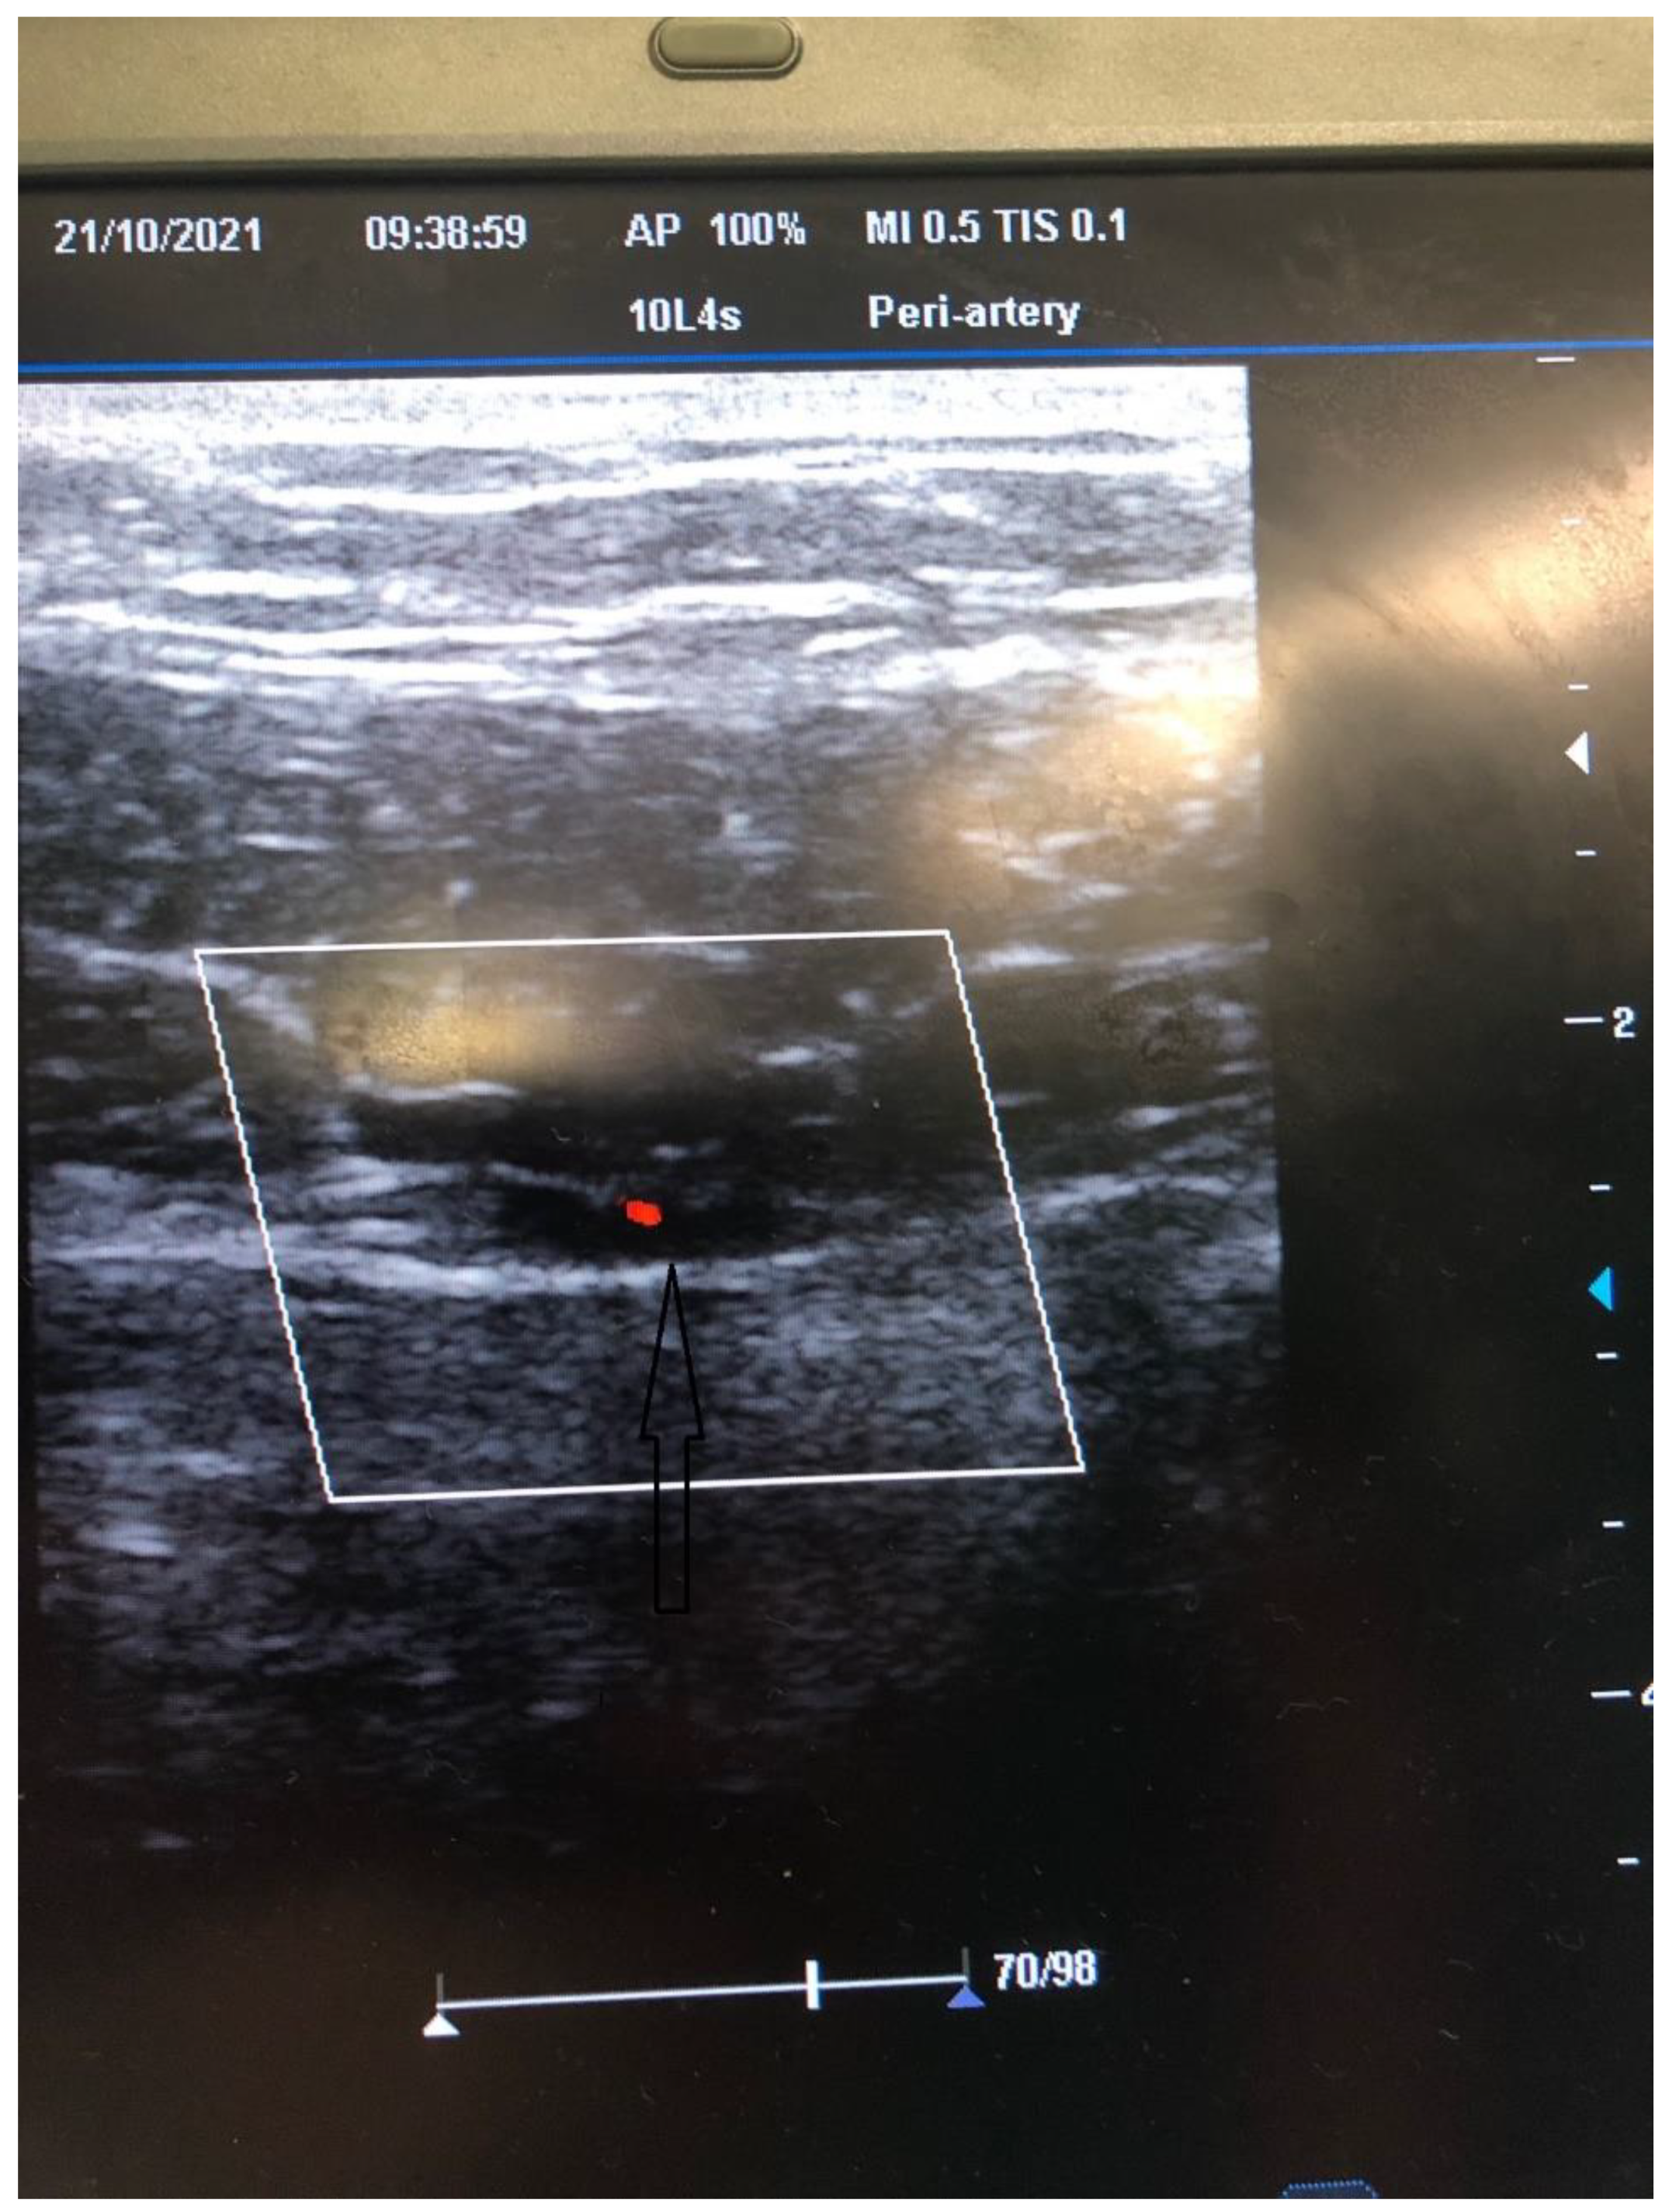

Figure 3.

US Doppler evaluation of the course of the inferior epigastric artery.

In all candidates for peritoneal dialysis (PD), a laparoscopic insertion of PDC under general anesthesia has been performed in our institution for the past 15 years. Recently, we implemented a modified technique with intraoperative US evaluation of the abdominal wall on the side of PDC insertion. The abdominal surgeon performs all PDC insertions under general anesthesia, while the nephrologist joins the surgery to perform an US of the abdominal wall. The side of PDC is agreed upon with patients preoperatively after obtaining informed consent. The patient is placed supine, and a single preoperative antibiotic prophylaxis with 1 g to 2 g cefazolin is given 30 min before the skin incision. If a penicillin allergy is known, patients get 500 mg of vancomycin. The sterile operative field is prepared per standard protocol. Thereafter, the position of the internal cuff and a skin exit site are marked. The coiled Tenckhoff catheters with two dacron cuffs and a special trocar are used for rectus sheath tunneling. When the procedure is commenced, an US evaluation of the abdominal wall is performed ipsilaterally to the PDS insertion into the abdominal cavity. (Figure 1). The rectus abdominis muscle width is measured with the US (Figure 2), and the course of the inferior epigastric artery is determined with colored US Doppler (Figure 3). On the abdominal wall, the thickest part of the rectus abdominis muscle and the course of the inferior epigastric artery are both marked with a pencil (Figure 4). After that, the position of the internal cuff is determined 2–3 cm laterally from the umbilicus, where the rectus muscle is sufficiently thick. The positions of the external cuff and the skin exit site are also marked on the skin before insertion. After the US evaluation of the abdominal wall is completed, the laparoscopic insertion of PDC is performed. A standard laparoscopy is performed with one 5 mm trocar above the umbilicus and a 5 mm 30-degree camera. The second 5 mm trocar is inserted laterally as a working trocar for a laparoscopic grasper. The 5 mm skin incision is initially performed above the umbilicus, and a Veress needle is blindly introduced into the abdominal cavity. Aspiration and a water drop test is performed to ensure that the Veress needle is properly inside the peritoneal cavity. Pneumoperitoneum is created with CO2, and the intraabdominal pressure is maintained around 12 mm Hg, as in standard laparoscopy. A 5 mm trocar is blindly introduced into the abdominal cavity at this site. Although all patients have preoperative abdominal US performed, we further perform diagnostic laparoscopy with a 5 mm 30-degree camera to exclude any other associated intraabdominal pathology. Contralateral to the PDC insertion, another 5 mm trocar is inserted under laparoscopic vision and a camera is moved to that trocar so that the entry site of the catheter into the peritoneal cavity can be visualized during insertion. The patient is tilted to a slight Trendelenburg position, thus allowing a better exposure of the deep pelvis, which is the point for inserting the PDC tip. The Trendelenburg position enables the small bowel loops to retreat from the pelvis so that the pelvis can be further inspected for possible adhesion. The advantage of laparoscopy is also to enable advanced laparoscopic procedures, such as adhesiolysis if needed. Thereafter, the 1 cm skin incision is performed ipsilateral to the side of PDC placement, and a special trocar is used for rectus sheath tunneling. Because of the preoperative US evaluation of the abdominal wall, we are aware of the inferior epigastric artery course, so we can accommodate the rectus sheath tunneling course so as to avoid vessel injury and bleeding. Rectus sheath tunneling is performed with a special trocar, through which the PDC is then inserted into the abdominal cavity. The trocar is introduced under a 45-degree angle through a small skin incision into the subcutaneous tissue and is then blindly forwarded through the abdominal wall (Figure 5 and Figure 6). The peritoneum is penetrated under direct laparoscopic vision to avoid any bowel or large vessel injury. The PDC is introduced through the trocar into the abdominal cavity, and the trocar is removed. With an atraumatic laparoscopic grasper, the coiled tip of the PDC is placed into the deep pelvis and the inner cuff is placed preperitoneally under direct laparoscopic supervision. The PDC is exteriorized laterally, and the outer cuff is placed in the subcutaneous tissue. The distance between the outer cuff and the skin exit site should be 2–4 cm. At the end of the laparoscopy, the proper position of the PDC tip and potential bleeding from the peritoneum at the trocar and PDC breakthrough sites are rechecked, respectively. All trocars and working instruments are removed from the abdominal cavity, and the pneumoperitoneum is released. The PDC is flushed with 50 mL of normal sterile saline to ensure the fluid flows freely in and out of the abdominal cavity. The fascia at trocar sites is sutured, and skin incisions are sutured with 4/0 absorbable sutures. The latter are infiltrated with a local anesthetic. When the surgical part of the PDC insertion is completed, an US is performed again to check for a proper position of the PDC tip and inner cuff. The outer end of the PDC is connected to the titanium adapter and transfer set. The complete outer part of the PDC is covered with gauze and transparent dressing. Following the procedure, the patient is admitted to the nephrology department, where a small volume flushing (200–500 mL) is started the next day. According to our institutional protocol, after laparoscopic insertion of the PDC, all patients have to wait 4–6 weeks before a full PD is commenced to achieve full healing of both the skin and abdominal wall wounds at trocar sites, thereby preventing (or minimizing) the possible leak. The patient is advised to avoid heavy lifting and strenuous physical activity for 4–6 weeks after the procedure.

The laparoscopic technique of PDC insertion is a well-known and established technique for PDC placement. The intraabdominal placement of the PDC is performed under the direct vision of a laparoscope, which helps to avoid injury to the bowel and to place the PDC tip correctly in the deep pelvis. A critically important component of PDC placement is a proper rectus sheath tunneling with a special trocar, which is performed blindly, without guidance on the location of the major vessels and where the rectus muscle is sufficiently thick for the proper placement of the internal cuff that should lie within the rectus sheath preperitoneally [5]. The other possible complication of rectus sheath tunneling is an injury of the inferior epigastric artery with major bleeding, which can require a more aggressive approach, such as laparotomy, to arrest bleeding. A crucial step in PDC placement is the proper position of the internal and external cuff and proper exteriorization of the PDC. The internal cuff should not slip into the abdominal cavity, which can be seen and repaired during laparoscopy. However, during laparoscopy, we cannot see if the internal cuff is placed properly within the rectus sheath. In patients with a very thin abdominal wall and thin rectus muscle, the internal cuff can slip out of the rectus sheath into the subcutaneous tissue, which can be seen with US and not with laparoscopy. The proper position of the internal cuff is essential for the proper incorporation of the PDC into the abdominal wall, which reduces the possibility of a pericatheter dialysate fluid leak and potential PD failure [6]. The advantage of inserting the catheter through the thickest part of the muscle is that the internal cuff has more place to be incorporated within the rectus muscle. If the patient has a thin abdominal wall with a weak rectus muscle, the internal cuff is pulled through the muscle and incorporated preperitoneally to provide the optimal position and prevent a possible leak of dialysate fluid.

In our experience, US guidance is of great benefit for correctly positioning the PDC into the abdominal wall. It allows us to determine the thickest part of the rectus abdominis muscle and the ideal site of the internal cuff position within the rectus sheath. In addition, the US-Doppler can help to identify the course of the inferior epigastric artery and its major branches and thus helps avoid major bleeding during surgery. After the PDC insertion, the US helps us to check the proper position of the internal cuff and to correct the position if necessary [7]. Although the laparoscopic technique is very effective and safe, it does not preclude complications during blind rectus sheath tunnelling. Hence, we opted to modify our previous technique to ensure the safest and most effective approach. Moreover, we noticed increased pericatheter dialysate fluid leaks in our last 40 patients. All these patients were evaluated with US, and in a few of them, we observed the internal cuff either displaced into the subcutaneous tissue or placed in a suboptimal place within a very thin rectus muscle. Besides the technical failure, other factors predispose to a pericatheter leak, such as a thin abdominal wall, bad tissue healing, and other patient conditions. Hence, we decided to optimize the technical aspect to perform the most optimal PDC insertion. We believe that the afore-described technique presents a step forward, and we see a great benefit of it in providing the most optimal PDC insertion while reducing the technical failure of PD. We believe that combining preoperative and intraoperative US evaluation of the abdominal wall with concurrent use of laparoscopy is the safest and most effective technique of PDC insertion. However, so far, we have performed the modified US-guided technique in only a few of our patients, and we do not have data on long-term results. Due to the small number of patients, at the moment, we cannot objectively evaluate the results and compare both techniques.